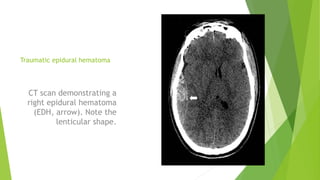

Traumatic epidural hematoma

CT scan demonstrating a

right epidural hematoma

(EDH, arrow). Note the

lenticular shape.

Traumatic epidural hematoma CTscan demonstrating a right epidural hematoma (EDH, arrow). Note the lenticular shape.

• #10 Extra-axial (defined as outside the substance of the brain) hematomas are generally encountered when forces are distributed to the cranial vault and the most superficial cerebral layers. These include epidural, subdural, and subarachnoid hemorrhage. In adults, epidural hematomas (EDH) are typically associated with torn dural vessels such as the middle meningeal artery, and are almost always associated with a skull fracture. EDHs are lenticular-shaped and tend not to be associated with underlying brain damage. For this reason, patients who are found to have EDHs only on CT scan may have a better prognosis than individuals with other traumatic hemorrhage types. &amp;lt;number&amp;gt;